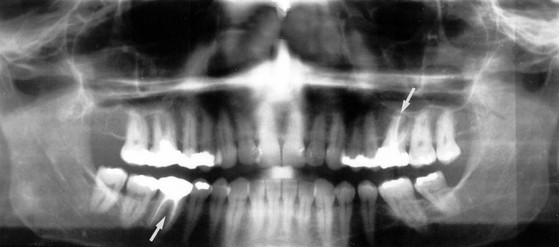

Fig. 48.2 Dental restorations and root fillings

This oral pantomograph (OPG) film shows silver amalgam restorations for caries in posterior teeth (shown as white radiopacities) and synthetic resin restorations in front teeth (relative radiolucencies in the upper incisors). In addition, the upper left first molar and the lower right first molar (arrowed) have radiopaque root canal fillings, necessitated by dental caries invading the pulp